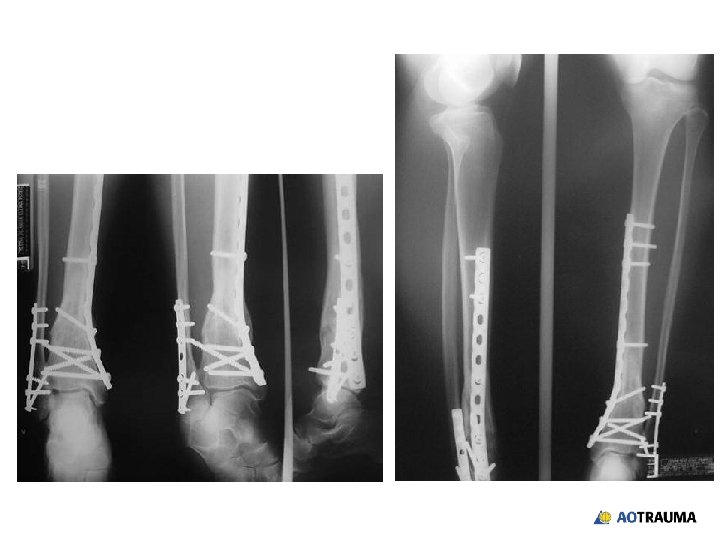

32 -year-old male, motor vehicle accident, open grade II

Reduction and fixation? 1. Closed indirect reduction and IM nailing 2. Closed indirect reduction and plate fixation 3. Closed indirect reduction and external fixation 4. Open direct reduction and plate fixation

Wound healed—what now? 1. Continue with external fixation 2. Closed reduction and retrograde nail 3. Closed reduction and locked plate 4. Open reduction and plating